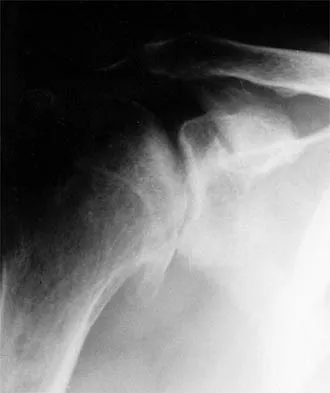

Figure 46 shows the AP radiograph of a patient with right shoulder pain. What is the most likely diagnosis?

Posttraumatic osteolysis of the distal portion of the clavicle is a condition that can be a complication of acute or repetitive trauma. The distal end of the clavicle is frayed and resorbed. Resorption may occur after weeks or months. The end of the clavicle may reconstitute over a period of months, or the acromioclavicular joint may remain widened. The differential diagnosis for distal clavicular erosion also includes rheumatoid arthritis, hyperparathyroidism, neoplastic destruction, cleidocranial dysplasia, and pyknodysostosis. Acutely, a type 2 acromioclavicular joint injury does not result in erosion or resorption of the clavicle. Periosteal sleeve injuries radiographically mimic acromioclavicular joint dislocation. Rickets occurs only in childhood.